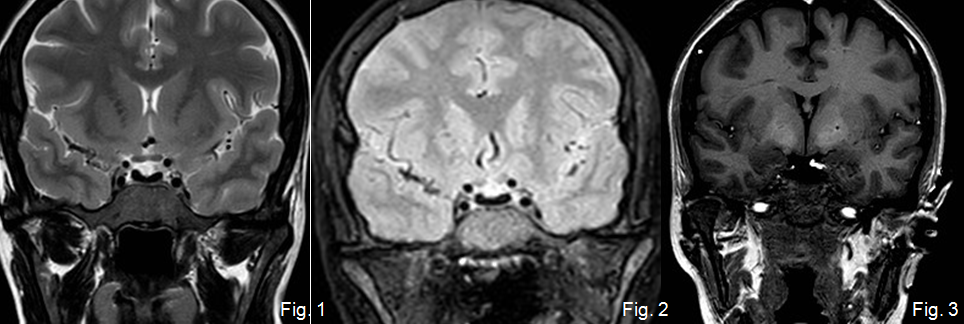

El diagnóstico diferencial se haría con tumores neurogénicos del trigémino.